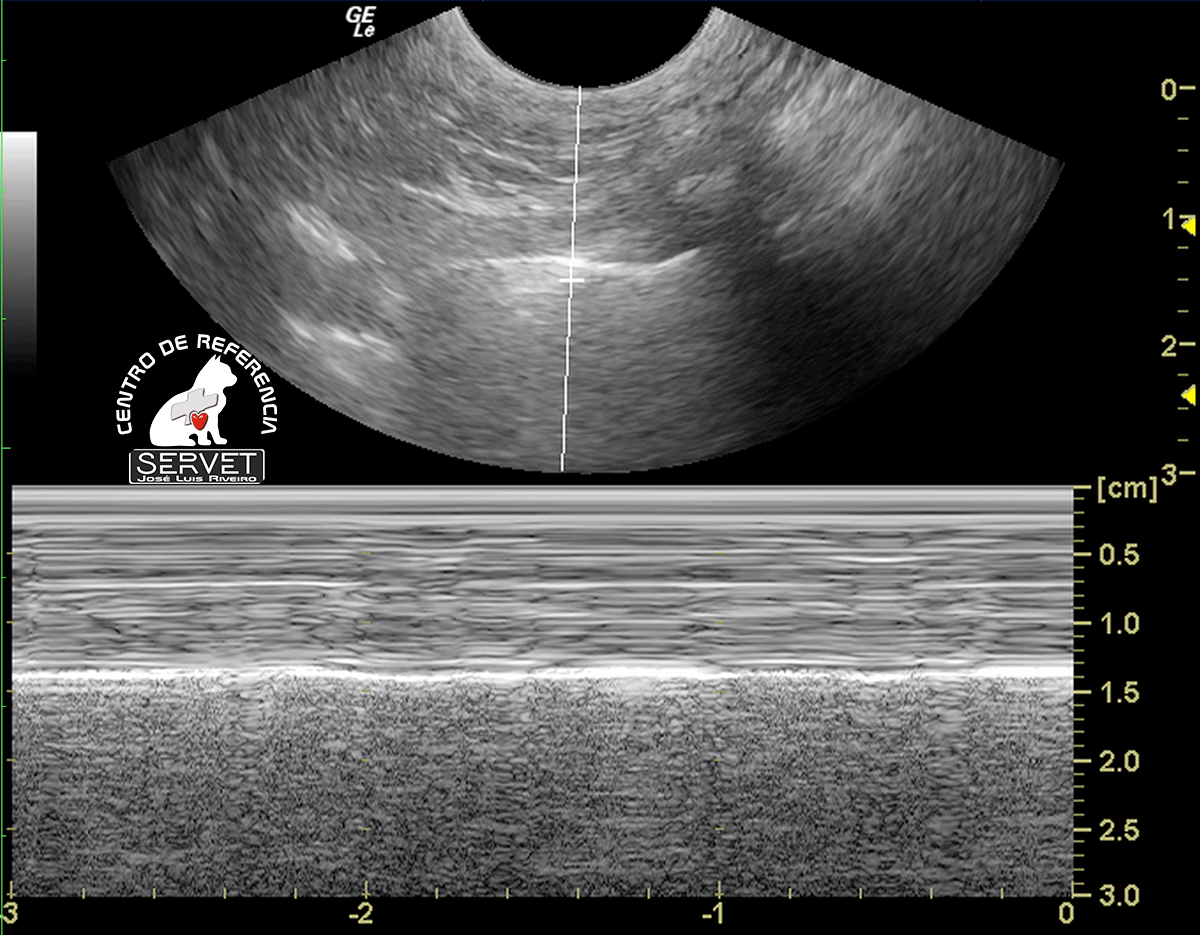

Seashore sign – pulmón normal

Si aplicamos el modo M sobre una ecografía pulmonar, se distinguen 2 zonas bien diferenciadas, que configuran el signo de la orilla (seashore sign): la parte superior, que corresponde a la pared torácica, formada por líneas horizontales paralelas (las olas del mar), y la parte inferior, desde la pleura (línea hiperecogénica a 1,4 cm de profundidad), de aspecto granulado (la arena de playa).